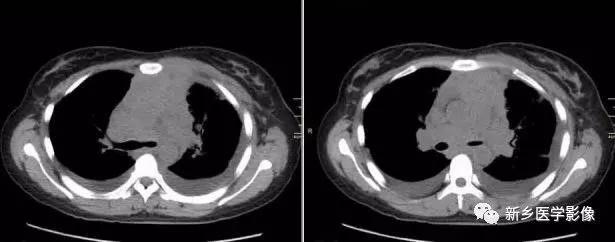

2.CT表现:前纵隔、中纵隔多组淋巴结肿大,常融合成块,尤其易累及血管前间隙组、主动脉弓旁、上腔静脉后组为最多见,易包绕上腔静脉等大血管及气管。肿块多呈均匀软组织密度,分叶状。轻到中度强化。放疗后肿块内易出现坏死、囊变、钙化灶。病人多伴有全身其他部位的淋巴结肿大。